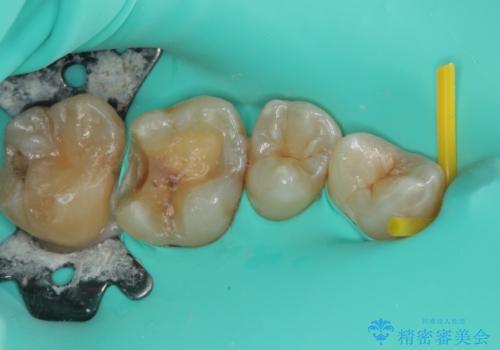

- 左上の前から5番目の金属の詰め物(メタルインレー)が取れたとのことで来院された患者様です。一時帰国中とのことで短期間での治療を希望されていました。土台はファイバーコアがしっかり入っていたため、そのまま利用することにしました。根管治療は症状もなく、レントゲン上でも病変を認めないため患者様と相談して根管治療を行わないことにしました。拡大鏡の視野下において、虫歯を除去して元々の詰め物の範囲も大きいためオールセラミッククラウンに適した形に整えました。

型どりは、シリコーン印象材にて印象しています。